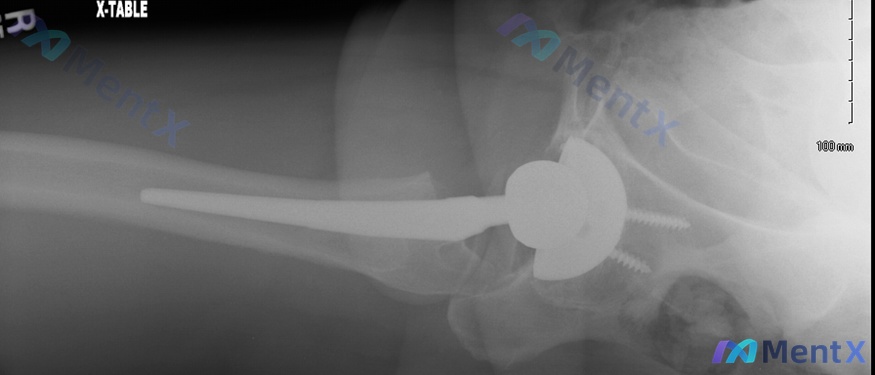

整理到一份82岁男性的骨科病例资料,有点意思,不是简单的“骨折了选什么固定”。 > 基本情况:82岁男性,从站立高度跌倒后就诊。 > 影像关键发现: > 1. 右侧人工全髋关节置换术后状态 > 2. 股骨假体柄远端周围股骨干骨折,斜形分离,远端向内侧移位 > 3. 假体周围骨皮质有萎缩/透亮带 >...

今天看到一个挺有警示意义的全髋置换术后病例,整理一下资料和思考逻辑,和大家一起讨论。 病例基本情况 - 患者:78岁男性 - 背景:右全髋关节置换术后4个月 - 诱因:在家中摔倒 - 主诉/体征:右腿畸形、疼痛,无法负重 - 重要阴性:否认跌倒前经历过任何腹股沟疼痛 关键影像表现 (参考提供的 X...